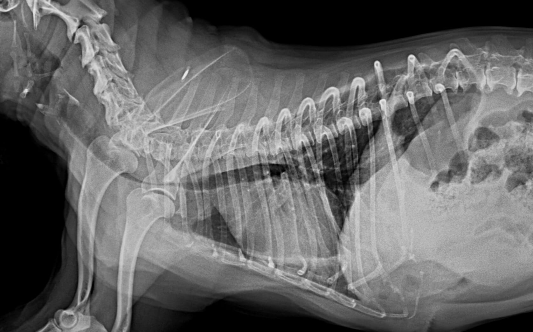

- 방사선 촬영: 방사선 촬영은 기관의 모습을 볼 수 있고 기관 허탈을 진단하는데 도움이 됩니다.